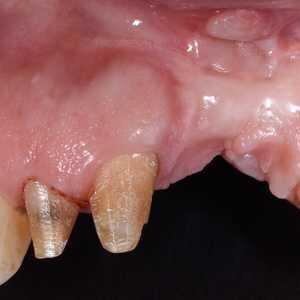

Dans cet article, nous présentons un cas clinique qui montre comment une mauvaise mise en place d'un implant peut rendre impossible la réhabilitation prothétique, ce qui nécessite une nouvelle planification chirurgicale et de réhabilitation pour obtenir l'esthétique souhaitée. Le patient se présente à notre observation avec une réhabilitation prothétique incongrue, avec bride en résine, support dentaire et implantaire, avec la présence d'un implant en position 2.1 vestibulaire et avec l'émergence dans le fornix, dans la mucosa alvéolaire. L'évaluation de la tomodensitométrie montre la position incorrecte de l'implant et la perte constante dans le sens transversal de la structure osseuse (Figs. 1, 2). Par conséquent, le plan de traitement suivant a été choisi : retrait de l'implant et préparation prothétique de l'élément 2.3, fabrication d'un premier support dentaire temporaire pour guider la cicatrisation des tissus (Figs. 3-7). Après 4 mois, une greffe d'épithélium conjonctif libre est réalisée avec ablation du palais pour compenser l'espace transversal des tissus mous, puis le provisoire est remodelé afin de faciliter la cicatrisation des tissus (Figures 8-11). Après 9 mois de maturation des tissus, la finalisation prothétique fixe avec support dentaire est réalisée (Figs. 12-14).